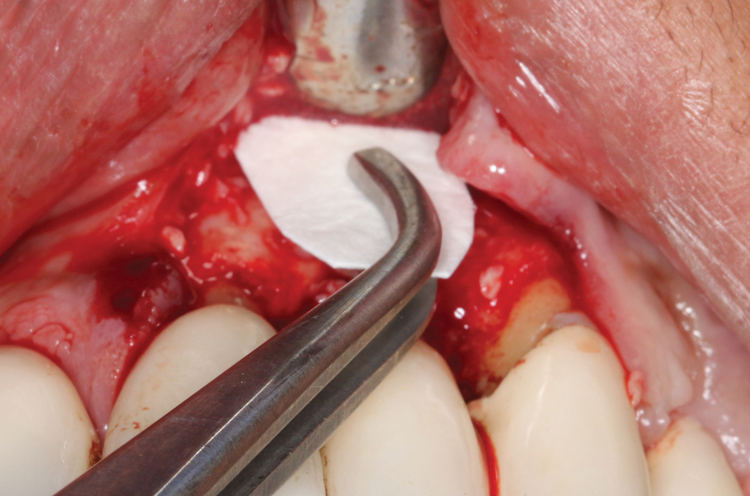

(4.) The diode laser tip was initiated with dark blue occlusal paper.

Figure 4

This is where the treatment became challenging. First, a curette was used to attempt to remove the granulation tissue from around the apex of the implant circumferentially. This was a difficult endeavor, especially on the palatal aspect of the site. Following curettage, an 810 nm diode laser (NV® PRO3, DenMat [alternatively: Picasso+, AMD Lasers; Gemini, Ultradent]) was used to treat the apical portion of the implant. After the laser tip was initiated using dark occlusal paper (Figure 4), it was used to debride the remaining necrotic tissue and decontaminate the entire site, reducing the bacterial count (Figure 5 and Figure 6).